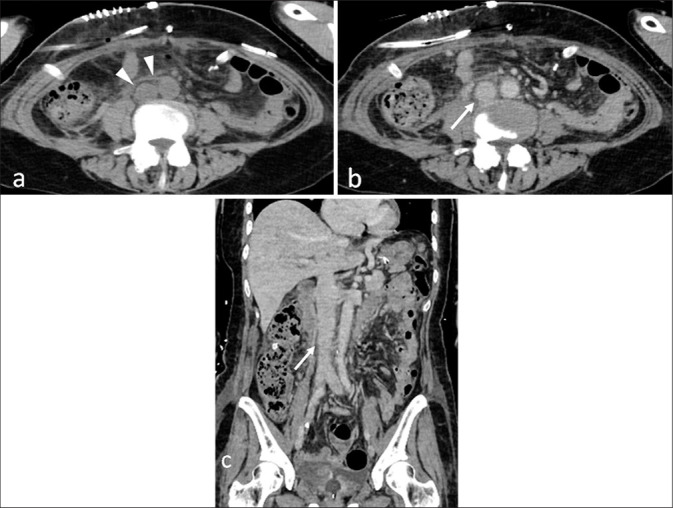

钝性外伤性下腔静脉(IVC)损伤是罕见的,提出了诊断和治疗的挑战。我们报告一例钝性外伤性下腔静脉损伤合并肠穿孔和脊髓损伤,成功地通过非手术保守治疗。一名57岁的妇女在一辆未系安全带的机动车碰撞中受伤。计算机断层扫描(CT)显示在肾下水平不规则的下腔静脉轮廓和腹膜后血肿,导致钝性外伤性下腔静脉损伤的诊断。腹腔内自由空气提示肠穿孔,磁共振成像证实C5/6脊髓损伤。这种伤害的组合可能会引起安全带伤害模式的怀疑。手术治疗肠穿孔,脊柱损伤后路固定。由于患者血流动力学稳定,下腔静脉损伤选择保守治疗。随访CT显示腹膜后血肿减少,下腔静脉轮廓改善,表明保守治疗成功。钝性外伤性下腔静脉损伤是罕见的,一些病例不表现造影剂外渗。在这个病例中,诊断是基于下腔静脉轮廓异常和腹膜后血肿。考虑到患者血流动力学稳定,选择保守治疗。仔细解读CT表现对诊断下腔静脉损伤至关重要,适当的临床判断是成功非手术治疗的关键。

Blunt traumatic inferior vena cava (IVC) injury is rare and presents diagnostic and therapeutic challenges. We report a case of blunt traumatic IVC injury associated with bowel perforation and spinal cord injury, successfully managed with non-operative conservative treatment. A 57-year-old woman sustained injuries in a motor vehicle collision with a seatbelt fastened. Computed tomography (CT) revealed an irregular IVC contour at the infrarenal level and a retroperitoneal hematoma, leading to the diagnosis of blunt traumatic IVC injury. Free intraperitoneal air suggested bowel perforation, and magnetic resonance imaging confirmed a C5/6 spinal cord injury. This combination of injuries may raise suspicion for a seatbelt injury pattern. The bowel perforation was surgically treated, and posterior fixation was performed for the spinal injury. Since the patient remained hemodynamically stable, conservative management was selected for the IVC injury. Follow-up CT revealed a reduction in the retroperitoneal hematoma and improvement in the IVC contour, indicating successful conservative treatment. Blunt traumatic IVC injury is rare, and some cases do not exhibit contrast media extravasation. In this case, the diagnosis was based on IVC contour abnormalities and retroperitoneal hematoma. Considering the patient's stable hemodynamics, conservative treatment was selected. Careful interpretation of CT findings is essential for diagnosing IVC injury, and appropriate clinical judgment is key to achieving successful non-operative management in selected cases.